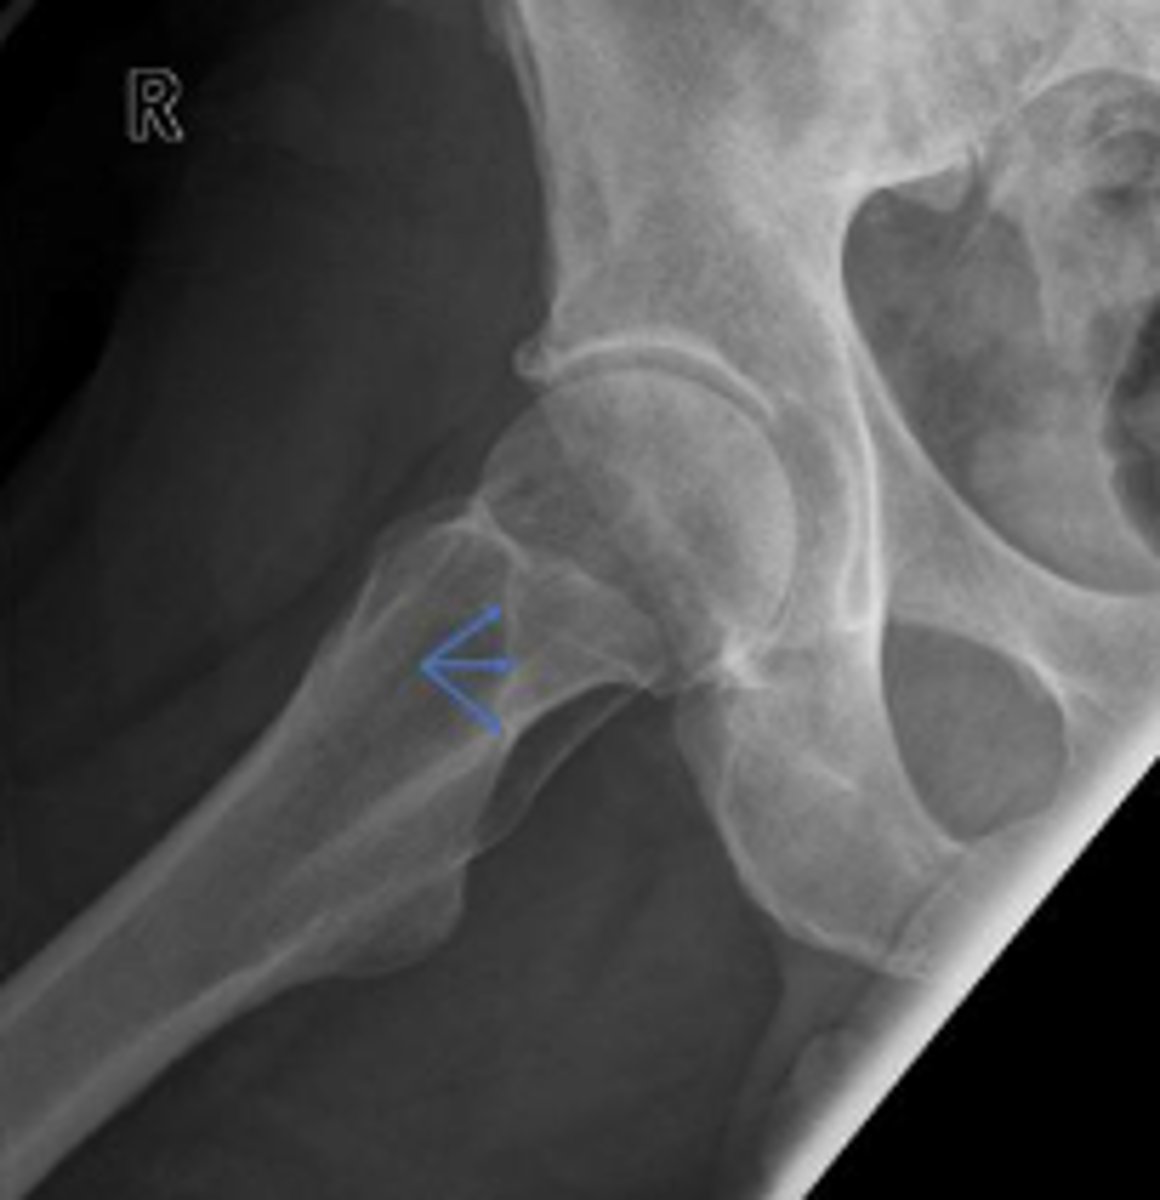

Right frog-leg hip

What is the name of the radiographic view?

Posterior rim of the right acetabulum

What are the arrows pointing to?

Anterior rim of the right acetabulum

Lesser trochanter of the right femur

Greater trochanter of the right femur

Right posterior inferior iliac spine

Intertrochanteric line of the right femur

Right ischial tuberosity